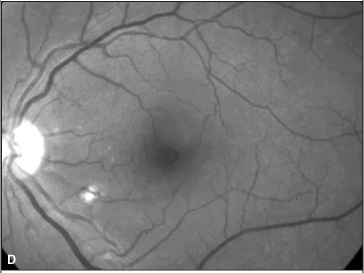

Foi suspenso o uso de interferon e o exame oftalmológico, após 4 semanas, revelou melhora na acuidade visual corrigida (olho direito = 20/50 e olho esquerdo = 20/20). A oftalmoscopia indireta e a biomicroscopia de fundus ocular revelaram diminuição importante da quantidade de exsudatos algodonosos, das hemorragias retinianas e da hiperemia de nervo óptico (Figura 2). O paciente relatou melhora acentuada da acuidade visual.

No caso aqui relatado, descreve-se a retinopatia por interferon peguilado, que difere da grande maioria dos casos relatados de retinopatia associada ao uso de interferon alfa ou beta convencionais. Chama também a atenção, neste caso, a manifestação ocular tardia, pois o paciente vinha fazendo uso da medicação há aproximadamente dois anos antes de desenvolver sintomas. A baixa da acuidade visual do olho direito ocorreu, provavelmente, por má perfusão capilar retiniana na região macular, evidenciada por alguns exsudatos algodonosos no pólo posterior, e também pelo acometimento do nervo óptico: a retinografia colorida revela hiperemia de disco óptico e borramento do seu bordo superior. Há pubicações que relatam acometimento do nervo óptico associado ao quadro de retinopatia(10). Tanto as alterações de pólo posterior quanto do nervo óptico não são evidenciadas nas retinografias tomadas após a suspensão da medicação.